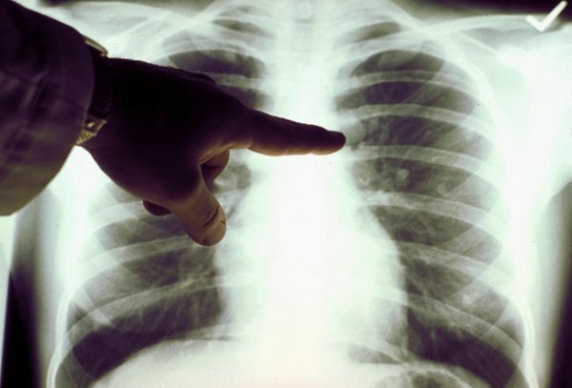

Alertă în Craiova! Are loc o anchetă epidemiologică la Școala Gimnazială nr. 32 „Alexandru Macedonski“ din cartierul craiovean Craiovița Nouă. Un cadru didactic a fost diagnosticat de curând cu TBC.Ca urmare a investigațiilor efectuate în astfel de cazuri, a reieșit că 40 de copii au valori mai mari decât cele normale la testul IDR, prezentând infecție tuberculoasă.

Medicii de la Spitalul Clinic de Boli Infecțioase „Victor Babeș“ au recomandat părinților internarea copiilor pentru investigații suplimentare, care să stabilească dacă au sau nu tuberculoză. Investigații medicale fac și cadrele didactice. Până acum însă nu este nici un caz suspect de TBC, potrivit radiocraiova.ro.